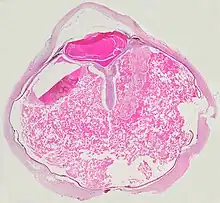

Pathologic findings

Grossly, retinal detachment and yellowish subretinal exudate containing cholesterol crystals are commonly seen.

Microscopically, the wall of retinal vessels may be thickened in some cases, while in other cases the wall may be thinned with irregular dilatation of the lumen.[10] The subretinal exudate consists of cholesterol crystals, macrophages laden with cholesterol and pigment, erythrocytes, and hemosiderin.[11] A granulomatous reaction, induced by the exudate, may be seen with the retina.[12] Portions of the retina may develop gliosis as a response to injury.